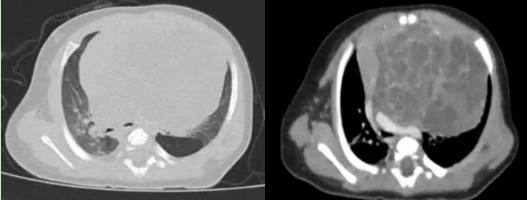

近日,一名僅2月齡、體重只有5.2kg的男嬰,因胸悶、呼吸困難來華西醫(yī)院小兒外科徐暢主任醫(yī)師處就診。經(jīng)CT檢查發(fā)現(xiàn),其縱隔內(nèi)有一個巨大腫塊,最大直徑 7.4×6.0cm,像胸腔里長一個巨大的“石榴”,嚴重壓迫心臟、左主支氣管及肺動脈,不盡快摘除,隨時可能引發(fā)呼吸循環(huán)衰竭,危及生命。

患兒胸部CT影像